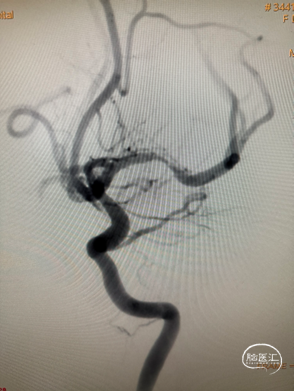

DSA

左侧大脑中动脉重度狭窄,近端:1.78mm,远端:2.18mm,最窄:0.25mm,长度:14.70mm,狭窄率约:89%。

支架释放后造影。

患者麻醉复苏后无神经功能障碍。患者术后标准正侧位造影。